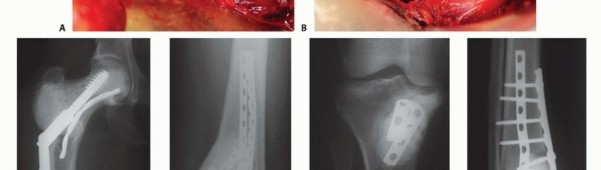

2. الجراحة التقليدية:

تعتبر الجراحة هي حجر الزاوية في علاج معظم أورام العظام، خاصة الخبيثة منها.

الجراحة الحافظة للأطراف (Limb Salvage Surgery):

تهدف إلى إزالة الورم مع الحفاظ على الطرف المصاب. تتضمن إزالة الجزء المصاب من العظم واستبداله بطعم عظمي، أو مفصل صناعي، أو طرف اصطناعي داخلي (Endoprosthesis). تتطلب مهارة جراحية عالية وتخطيطًا دقيقًا.

الكشط والعلاج المساعد (Curettage and Adjuvant Therapy):

تُستخدم عادة لأورام العظام الحميدة، حيث يتم كشط الورم من داخل العظم، ثم يتم استخدام مواد مساعدة مثل الفينول أو النيتروجين السائل أو الكي الكهربائي لتدمير أي خلايا ورمية متبقية.

5. العلاج بالتبريد (Cryoablation): النهج الثوري

يُعد العلاج بالتبريد، خاصةً بتقنية الصب المباشر بالنيتروجين السائل، ثورة حقيقية في علاج أورام العظام، حيث يقدم بديلاً فعالاً وآمنًا للجراحات الكبرى، مع الحفاظ على الطرف المصاب ووظيفته. يعتمد هذا النهج على تدمير الخلايا السرطانية عن طريق تعريضها لدرجات حرارة منخفضة جدًا، مما يؤدي إلى تجميدها وموتها.